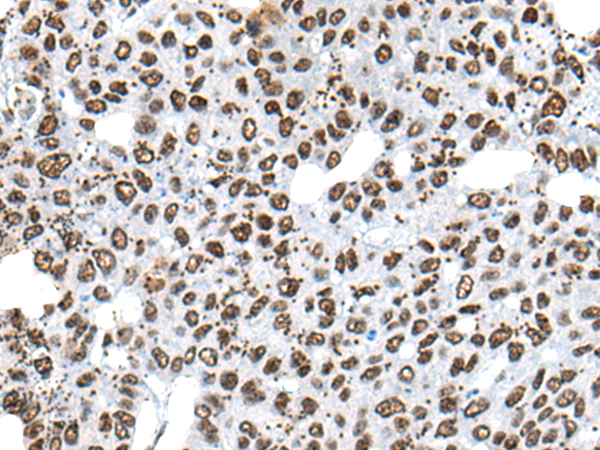

分类: 科研抗体货号: P13129别名: AMID; PRG3应用: IHC反应种属: Human, Mouse